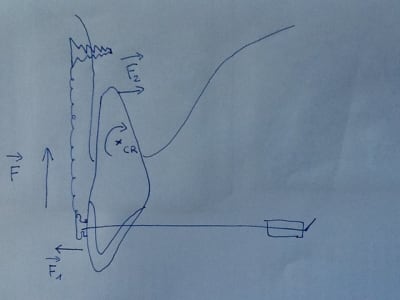

Au niveau biomécanique, si on applique une force d'ingression pure F sur un boitier vestibulaire, on crée un couple de rotation autour du centre de résistance CR de la dent. Ce qui provoque version vestibulaire coronaire F1 et palatine de l'apex F2.

Si tu bloques la version F1=0 en pliant par exemple le fil en distal des tubes molaires, on obtient alors une ingression et déplacement palatin de l'apex.

Pas besoin de mettre du torque dans le fil.